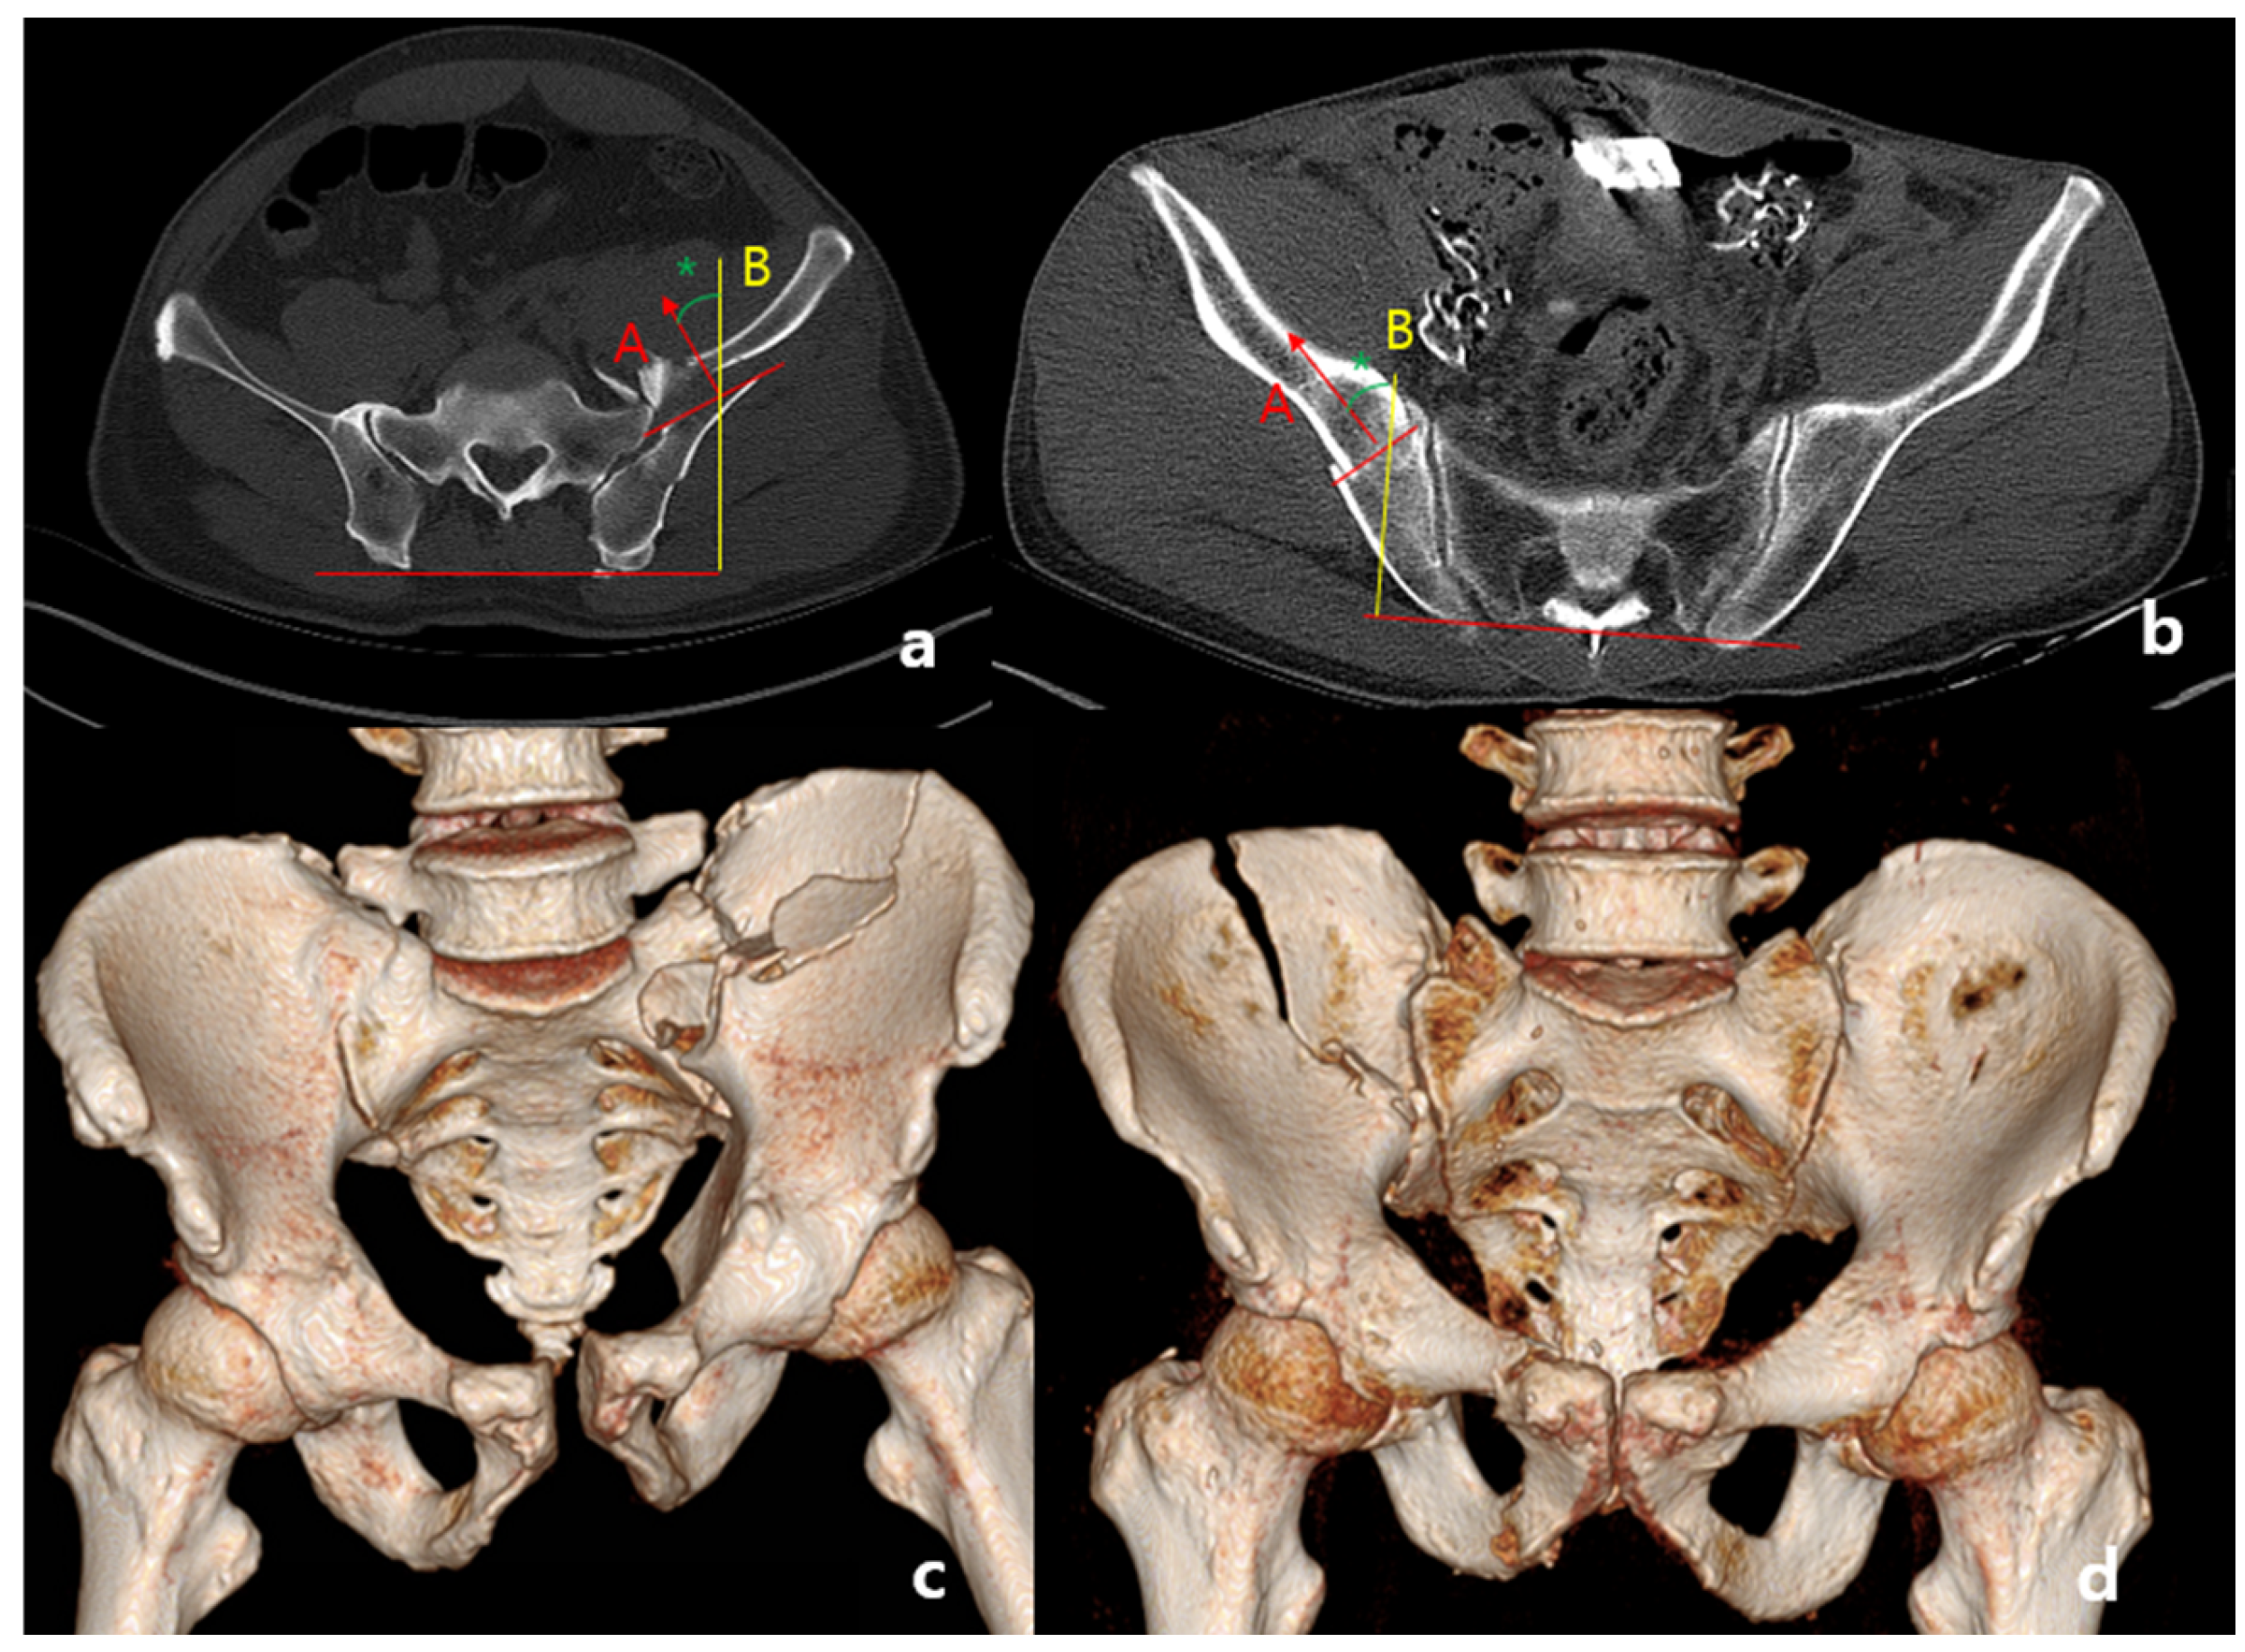

2.2. Definition of Anterior Sacroiliac Fracture Dislocation

2.3. Radiologic Assessment

2.4. Assessment of Vertical Displacement

2.5. Assessment of Rotational Displacement